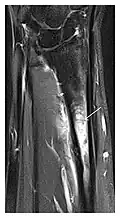

c

Figure 8: Proximal diaphyseal fatigue fracture of the tibia in a 20-year-old man with a history of regular jogging. (a) Lateral radiograph shows no obvious fracture lines but a subtle localized medial tibial cortex periosteal reaction (arrows). (b) Sagittal reformatted CT image acquired 1-month after the radiograph shows a linear hypoattenuation in the tibial cortex (arrowhead), as well as obvious periosteal thickening (arrows). (c) Sagittal T2-weighted fat-saturated image acquired the same day shows an area of hyperintensity spreading over the proximal tibia (arrows), which is consistent with the presence of proximal tibial fracture.[1]